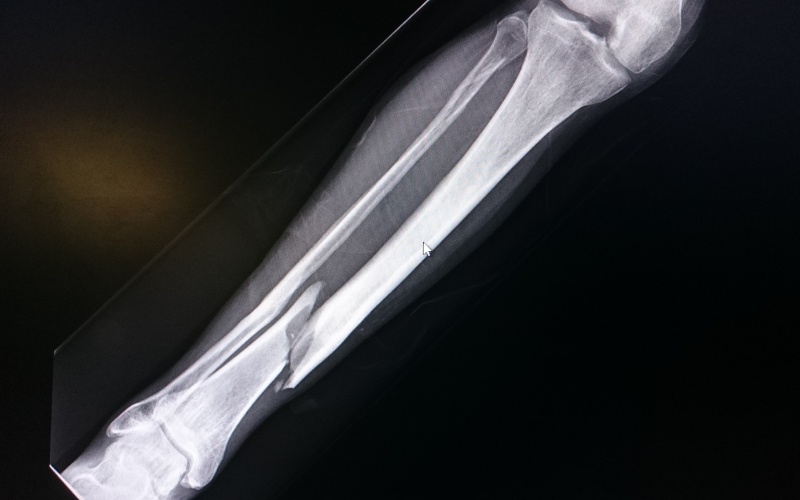

Osteoporosis causes bones to become thin, fragile, and more likely to break. It develops when the body loses bone faster than it can rebuild it. Age, hormonal changes, and lifestyle factors can speed up this process, leaving bones weak and prone to fractures.

A fracture is often the first warning sign. Hip and spine fractures can be especially serious, leading to pain, limited mobility, and long recovery times.

If a fracture is suspected, on-site imaging provides a fast and accurate diagnosis. This allows timely treatment without the need to visit multiple locations.

Fractures in the hip, wrist, or long bones may require surgical repair or fixation. Dr. Mehta uses modern techniques to promote safe bone healing while protecting surrounding tissues.